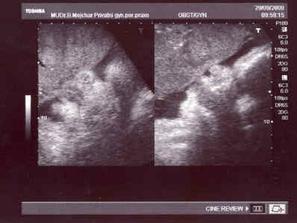

4.9. - na kontrole byl s námi i tatínek a beruška na nás pěkně plazila jazyk 🙂)...jsme pěkný obříci, vážíme už 2,7 kg :-O¨

15.9. - další kontrola, prvně nás pan doktor natáčel na monitor, vše je v pořádku a už vážíme 3 kg - fotku jsme tentokrát nedostali.

22.9. - další kontrola a beruška už váží 3,2 kg, na monitoru slaboučká kontrakce, která nebyla ani trošku poznat.

29.9. - další kontrola, beruška dosáhla porodní váhy 3,5 kg a na monitoru dvě slabé kontrakce...mamka zas nic nepoznala...